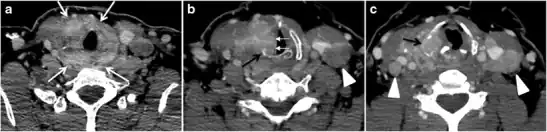

Fig. 11. Thyroid non-Hodgkin's large B-cell lymphoma in a 66-year-old female patient. an Axial enhanced neck CT scan demonstrates left thyroid lobe and isthmus homogeneously hypodense and minimally enhancing mass (white arrows). This lesion invades the prevertebral muscles (black arrows). Note the multiple enlarged level V lymph nodes (white arrowheads). b Post-treatment image shows significant reduction in size and mass effect of the left thyroid infiltrative mass, with almost complete resolution of the left cervical lymphadenopathy.[1] -

Fig. 12. Diffuse thyroid large B-cell lymphoma in a 79-year-old female patient. an Axial enhanced neck CT scan demonstrates a homogeneously hypodense and minimally enhancing large right thyroid solid mass (long white arrow) extending into the thyroid isthmus. It is encasing the right carotid artery (short white arrow) and displacing of the trachea and oesophagus to the left side.[1]

Thyroid lymphoma represents about 5% of thyroid malignancies. Non-Hodgkin's lymphoma is the most common type and can be secondary to generalized lymphoma or a primary tumour. Primary thyroid lymphoma usually pre-exists with Hashimoto's thyroiditis. On CT scans with and without contrast, lymphomas tend to have low attenuation values. Thyroid lymphomas have a variable appearance and mostly manifest as a solitary mass (80%). They may also manifest as multiple nodules (15% to 20%) or as a bulky mass replacing the entire gland with extra-thyroid extension (Figs. 11 and and12).12). The presence of cervical lymphadenopathy supports such a diagnosis. Although it is uncommon, tumour necrosis has been reported.[1]